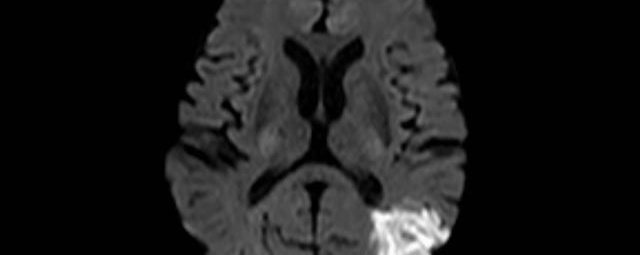

Kopf/Hals

• akute Schlaganfalldiagnostik und chronische Durchblutungsstörungen

• Diffusionswichtung

• Perfusionswichtung